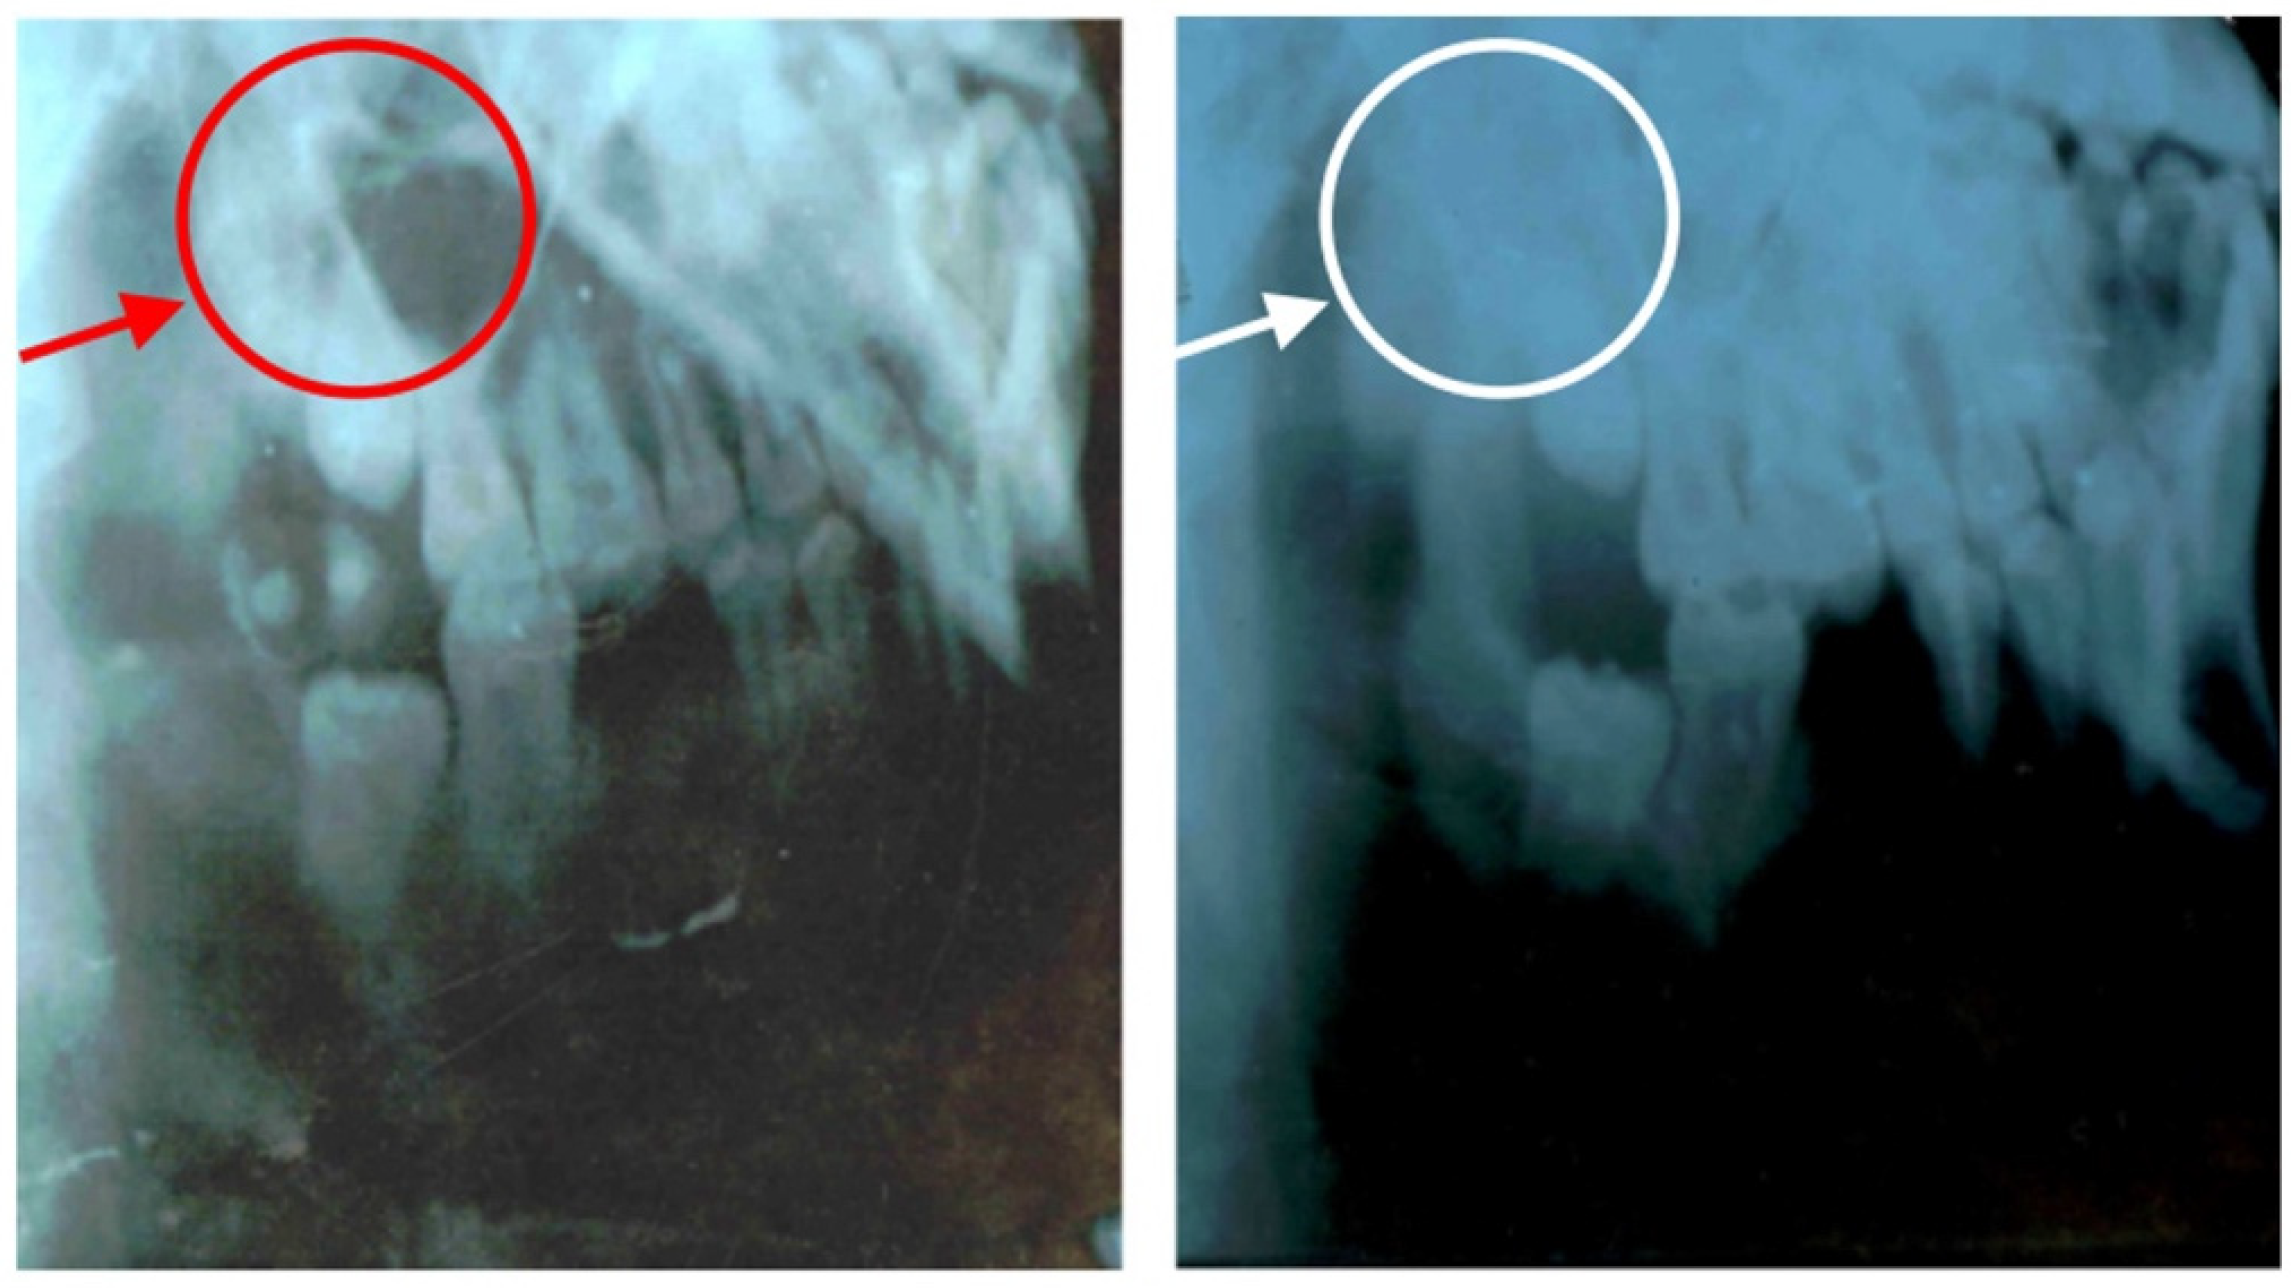

7.1. GC Dental Implants